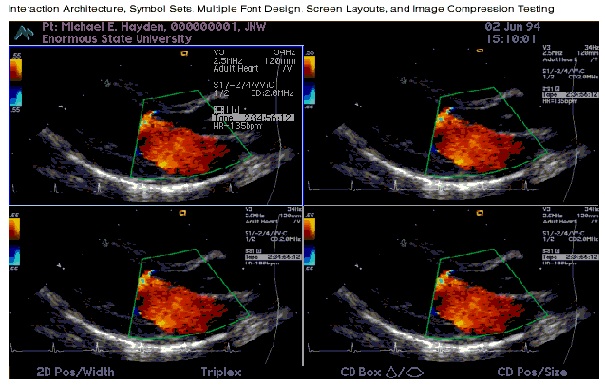

Echo Cardiogram & Exercise ECG

Echocardiogram (Echo) is a Test Uses High Frequency Ultra Sound Waves to Make Picture of Your Heart.

Echocardiogram (Echo) is a test, using high frequency ultra sound waves to make a picture of your heart. This test is also called diagnostic cardiac ultra sound. An echo uses ultra sound waves to create pictures of your heart's chambers, valves and the blood vessels attached to your heart. An echo can't harm you, you can eat and drink before the echo test as you normally would. Echo testing is done by a consultant cardiologist using GE brand echocardiogram machine Cardiac Investigations: Trooping I and T, B Type natriuretic peptide (BNP) assay is specially done for cardiac status.